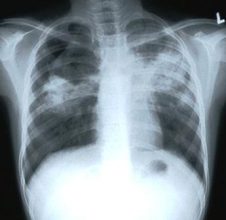

يوم السلّ العالمي التهوية والكمامات أبرز سبل الوقاية منه

صراحة – وكالات : يحتفل العالم بـ”يوم السلّ العالمي”، الأحد، في إطار التوعية بالمرض، وإتاحة خدمات التشخيص والعلاج والرعاية إتاحة شاملة لجميع المتضررين بمرض السل. فبحسب منظمة الصحة العالمية بلغ إجمالي عدد الوفيات بسبب السلّ…